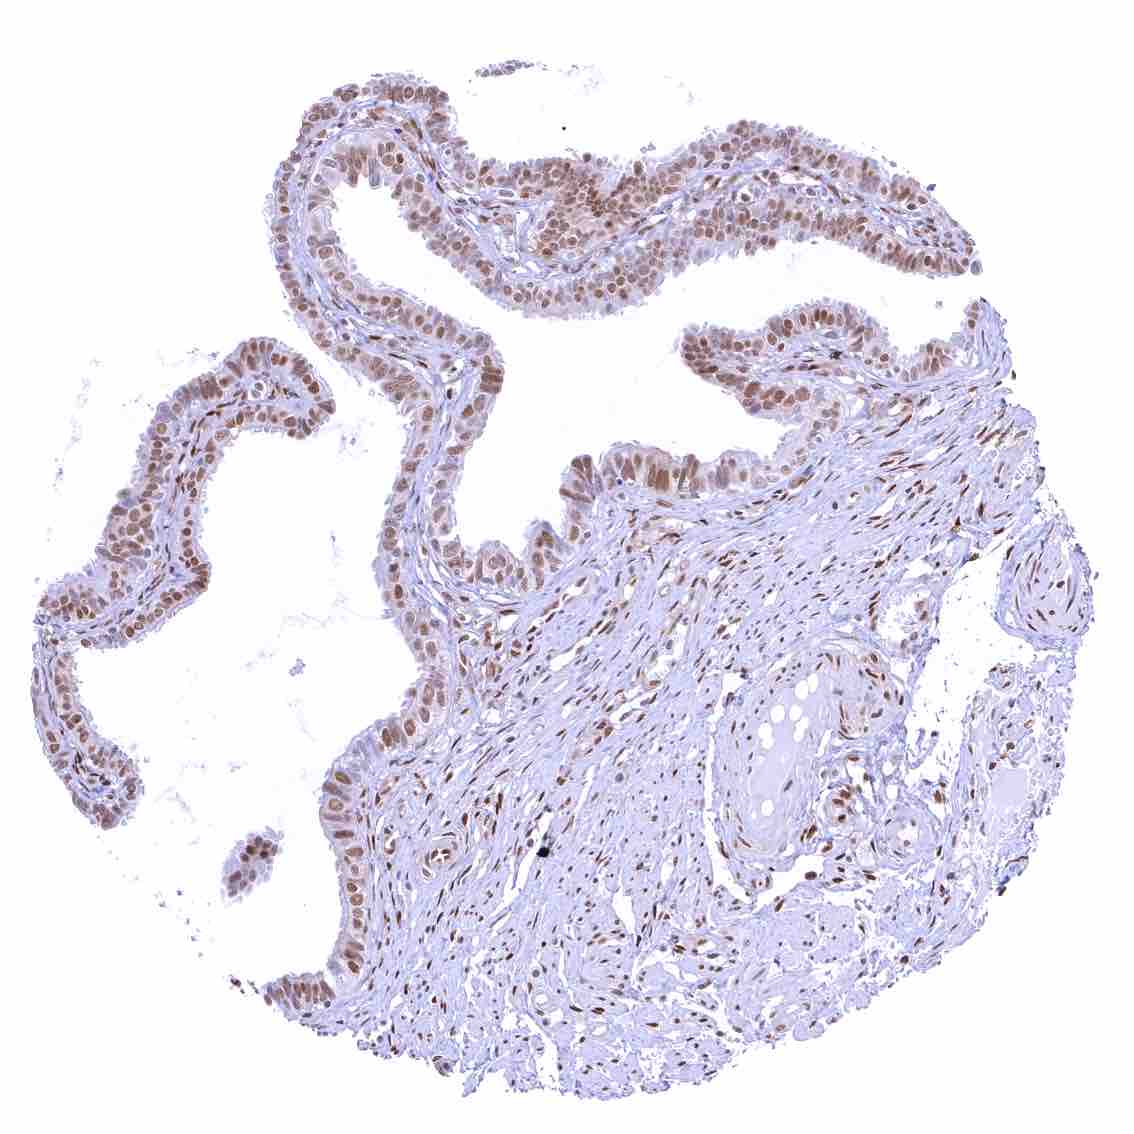

Bronchus, mucosa – Strong nuclear p27 positivity of a large fraction of respiratory epithelial cells.